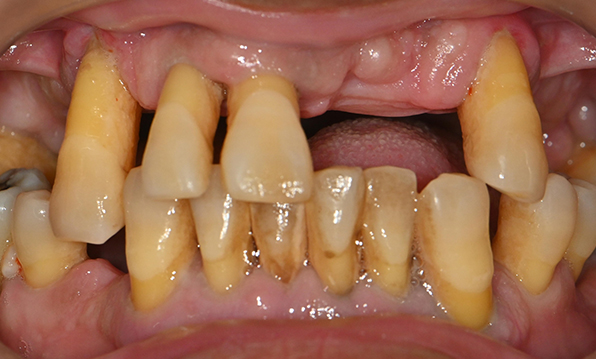

Case 03

Before After